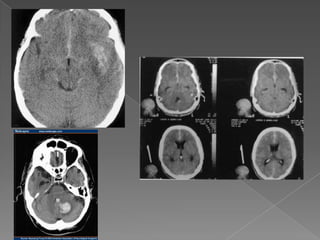

Grado 1: TC normal. Neurosurgery 1980;6:1-9

Grado 2: difusa o capa vertical < 1 mm Neurosurgery 1980;6:1-9

Grado 3: Coagulos localizados y capas > 1 mm. Neurosurgery 1980;6:1-9

Grado 4: Coágulo intracerebral o intraventricular. Neurosurgery 1980;6:1-9